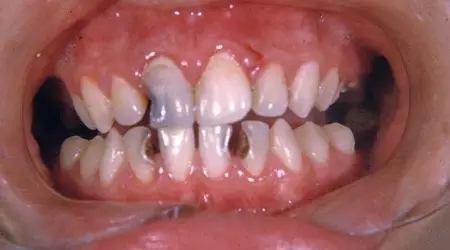

牙周炎

這十種常見口腔疾病,你有遇到過么?

牙周炎是牙周病的更高級形式,是成年人牙齒缺失的主要原因之一。據(jù)CDC統(tǒng)計,近一半的美國成年人患有牙周炎。雖然牙周炎早期階段可以逆轉(zhuǎn),但拖著不治療的時間越長,損害可能越永久。雖然牙周炎平??赡芨杏X不到,但一旦發(fā)生膿腫,通常會非常疼痛。

牙周炎的癥狀包括出血、牙齦腫脹、持續(xù)性口臭或口味差,恒牙松動以及咬合改變。隨著牙齦和牙槽骨萎縮,牙齒可能會看起來更長。

治療方法有許多,包括刮治和根面平整等深部清潔。與口腔醫(yī)生交流,讓他給你制定最適合的治療方案。